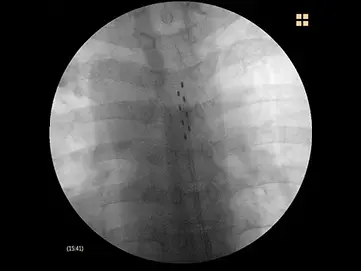

この治療では、まず皮膚を消毒し、局所麻酔を行います。症状の原因となっている神経根レベルの尾側から針を穿刺し、その中にスプリングガイドカテーテルを挿入し、造影を行いながら癒着部位に生理食塩水を注入するなどの操作で癒着を剥離します。

これらの原因の一つである硬膜外腔に生じた癒着を、スプリングコイルカテーテル(Raczカテーテル®等)と生理食塩水などを用いて剥離する治療法です。